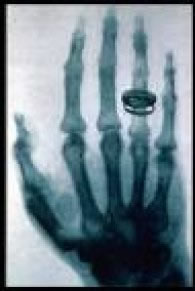

Radiografia da mão da esposa de Roentgen, realizada em 22 de dezembro de 1895. Esta é tradicionalmente conhecida ser “a primeira radiografia”.